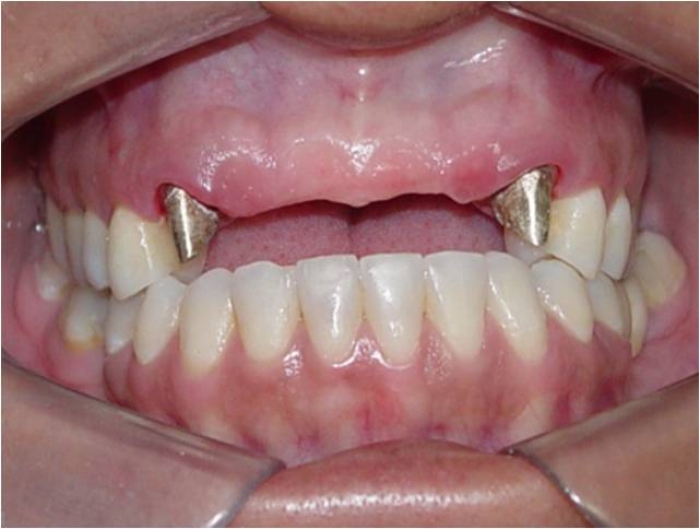

Imagem inicial

Próteses fixas em porcelana instaladas